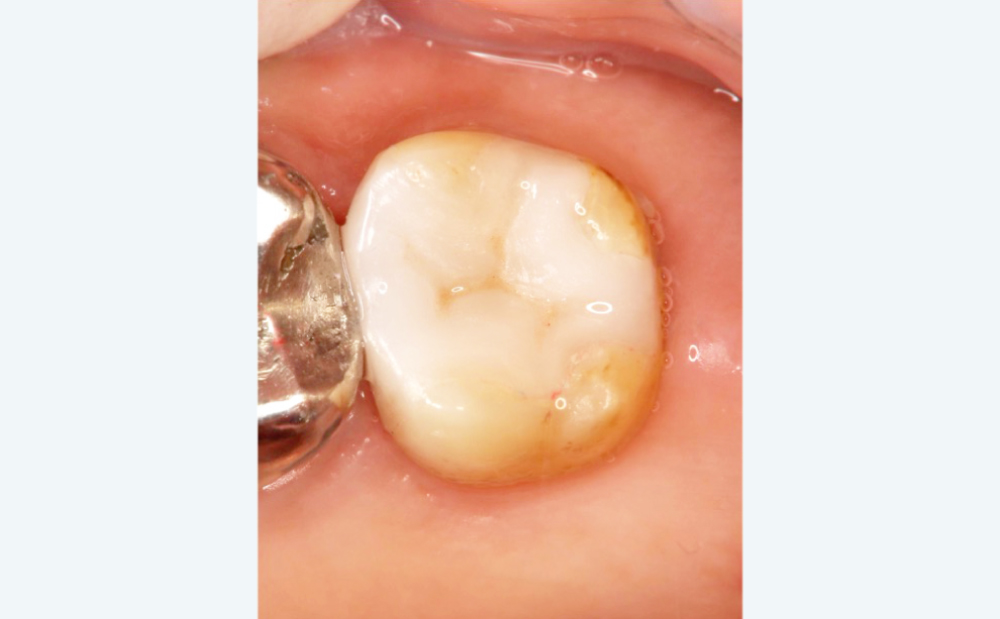

BEFORE

銀歯と歯の隙間から二次むし歯

銀歯と歯の隙間から二次むし歯

歯ぐきに軽度の腫れ

歯ぐきに軽度の腫れ

AFTER

根管治療で感染を除去

根管治療で感染を除去

ジルコニアクラウンで長期安定

ジルコニアクラウンで長期安定

清掃性が向上し、むし歯再発リスクが減少

清掃性が向上し、むし歯再発リスクが減少